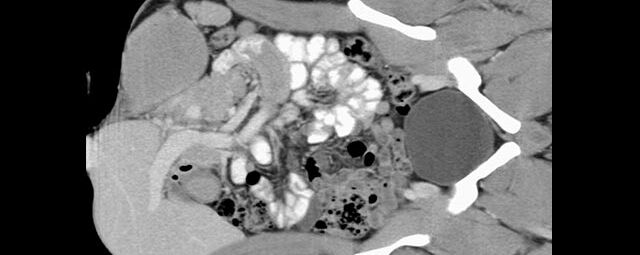

Abdomen (Bauch und Becken)

• Diagnostik von entzündlichen und tumorösen Erkrankungen der Bauchorgane

• Diagnostik von akuten Notfällen wie Darmverschluss, Hohlorganperforation oder Traumafolgen

• Darstellung der großen Gefäße zur Erkennung von Gefäßverschlüssen (z. B. Mesenterial - Arterienembolie oder Einengungen von Gefäßen (z. B. Nierenarterien)

• Darstellung und Therapieplanung von Aneurysmen (CT- Angiographie)

• Virtuelle Kolonographie zur Darstellung des Dickdarmes z. B. bei Kontraindikation zur Darm-Spiegelung oder nur unvollständig durchführbarer Koloskopie.